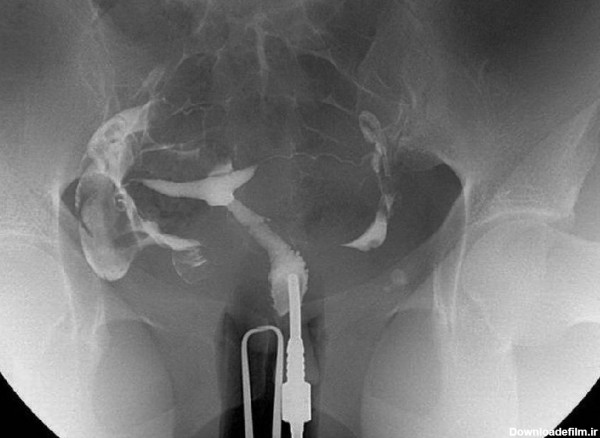

عکس رنگی رحم یا هیستروسالپنگوگرافی یکی از روش های تشخیصی شیوه ی تصویربرداری با اشعه ایکس است که معمولاً برای بررسی آناتومی رحم و لوله ها انجام میشود. عکس رحم

عکس رحم یا هیستروسالپنگوگرافی (Hysterosalpingography) چیست و بهترین زمان انجام عکس رنگی رحم و مزایا، عوارض، خطرات و کاربرد انجام آن چیست و چگونه انجام میشود

عکس رنگی رحم برای تشخیص علت ناباروری، بررسی لوله های فالوپ پس از عمل جراحی لوله ای یا پیوند مجدد لوله ای انجام می شود تا از بسته بودن لوله ها اطمینان حاصل شود.

عکس رنگی رحم چیست؟ یک آزمایش اشعه ایکس که برای بررسی رحم و لوله های فالوپ و ناحیه اطراف آنها نگاه می کند و برای بررسی مشکلات ناباروری ممکن است انجام شود.

عکس رنگی رحم (هیستروسالپنگوگرافی ) به ۲ صورت با بیهوشی و بدون بیهوشی انجام می شود. برای تشخیص اختلال رحم و سقط مکرر و ناباروری . جزییات کامل را بخوانید